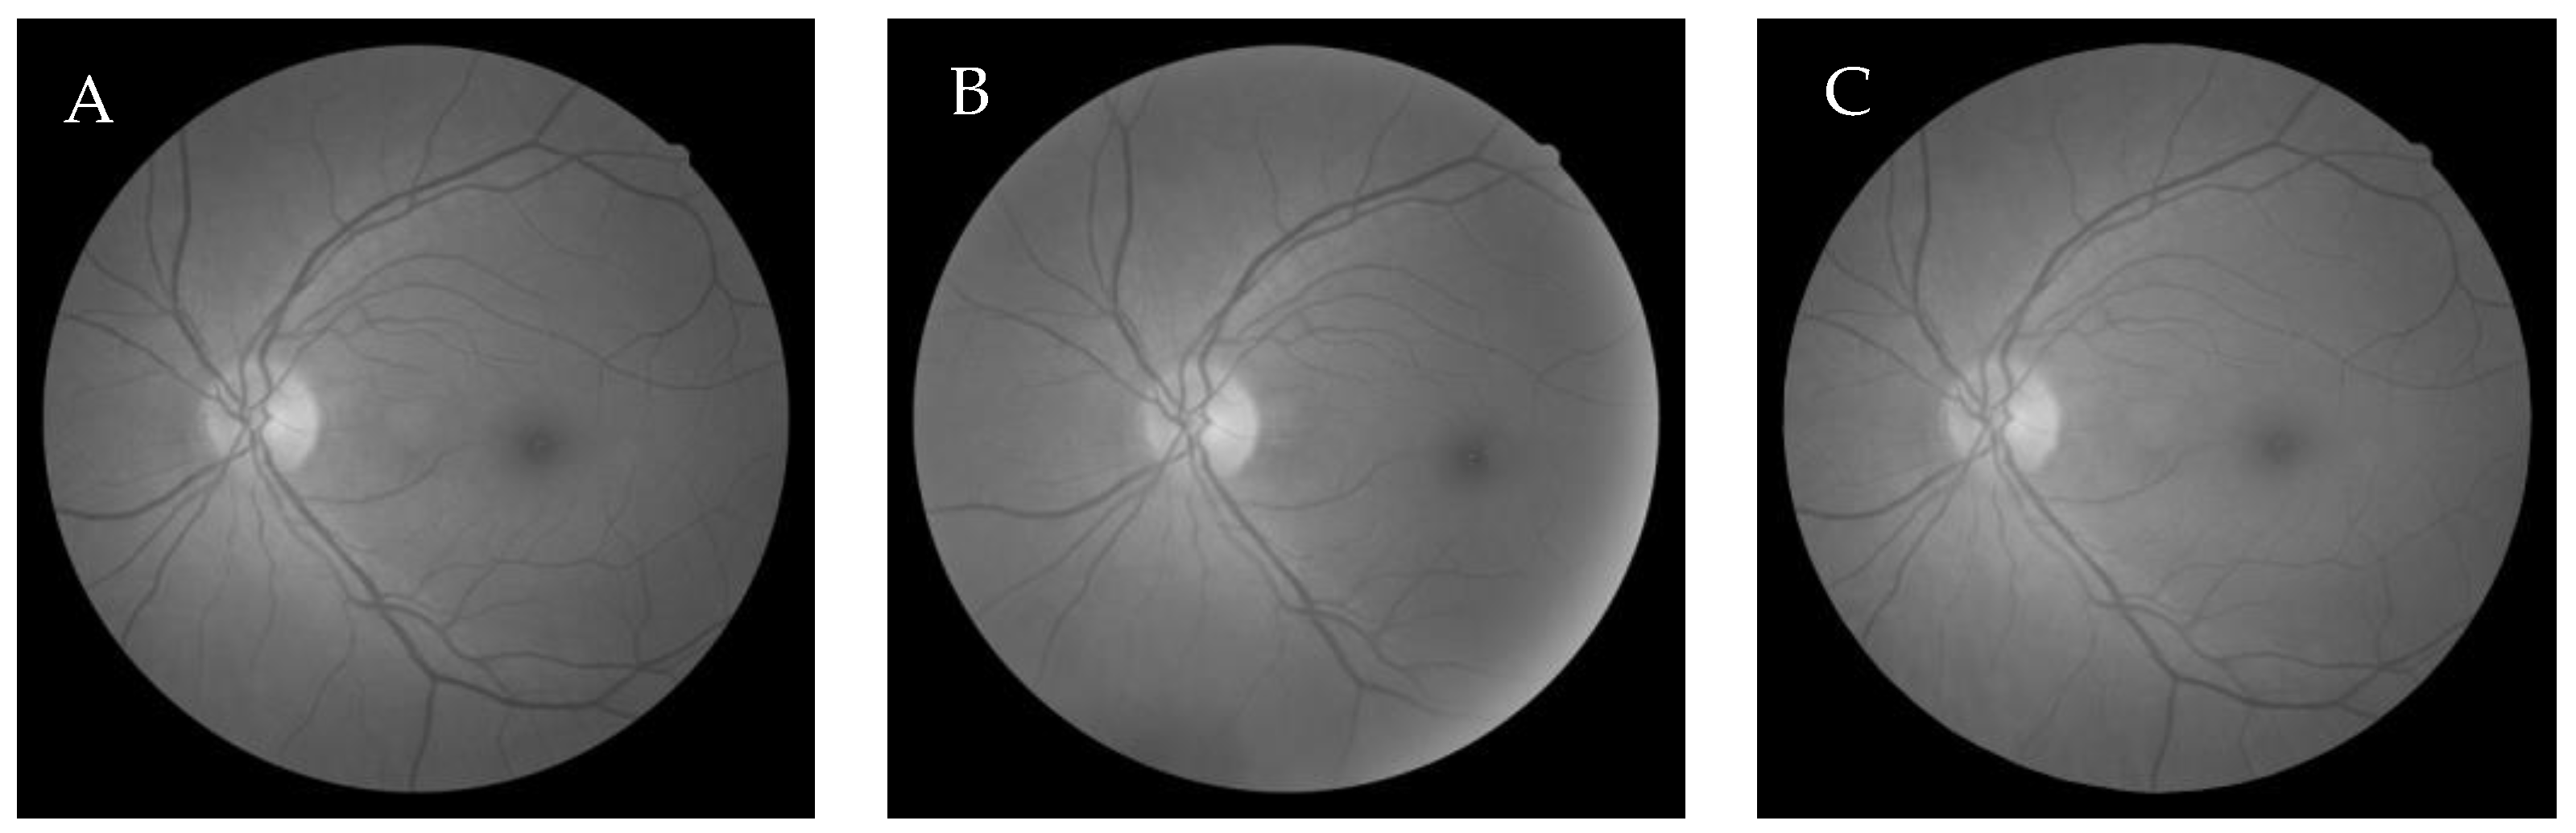

6.1. Dataset

6.2.3. Cuckoo search algorithm-based Wang’s Demons registration